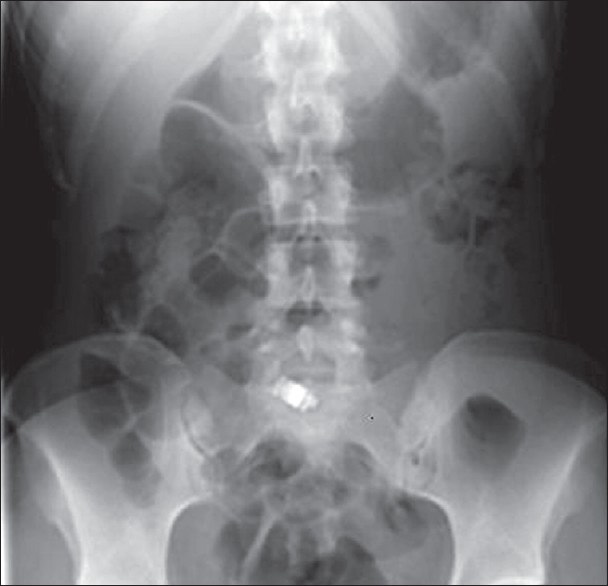

δ) Ενδοσκόπηση λεπτού εντέρου με ασύρματη κάψουλα και ενδοσκοπική κάψουλα βατότητας: Η βιντεοκάψουλα του λεπτού εντέρου χρησιμοποιείται στη διερεύνηση ασθενών με σιδηροπενική αναιμία ή υποτροπιάζουσες αιμορραγίες από το πεπτικό σύστημα «άγνωστης αιτιολογίας». Δηλαδή, οι ασθενείς έχουν υποβληθεί σε γαστροσκόπηση και κολονοσκόπηση, χωρίς ευρήματα που να δικαιολογούν την αναιμία ή την αιμορραγία. Τα συνήθη ευρήματα στους ασθενείς αυτούς είναι αγγειοδυσπλασίες, έλκη ή νεοπλάσματα του λεπτού εντέρου. Η εξέταση επίσης χρησιμοποιείται για τη διερεύνηση του λεπτού εντέρου ασθενών με νόσο Crohn ή κοιλιοκάκη και σε ασθενείς με οικογενή σύνδρομα πολυποδιάσεως. Η ενδοσκοπική κάψουλα βατότητας έχει το ίδιο μέγεθος με την ασύρματη, αλλά δεν βγάζει φωτογραφίες. Σε περίπτωση απόφραξης διαλύεται σε 5 ημέρες, από τα γαστρεντερικά υγρά, αφού ανιχνευθεί ακτινογραφικά η σκιογόνος ουσία που περιέχει και σηματοδοτηθεί το σημείο κωλύματος.